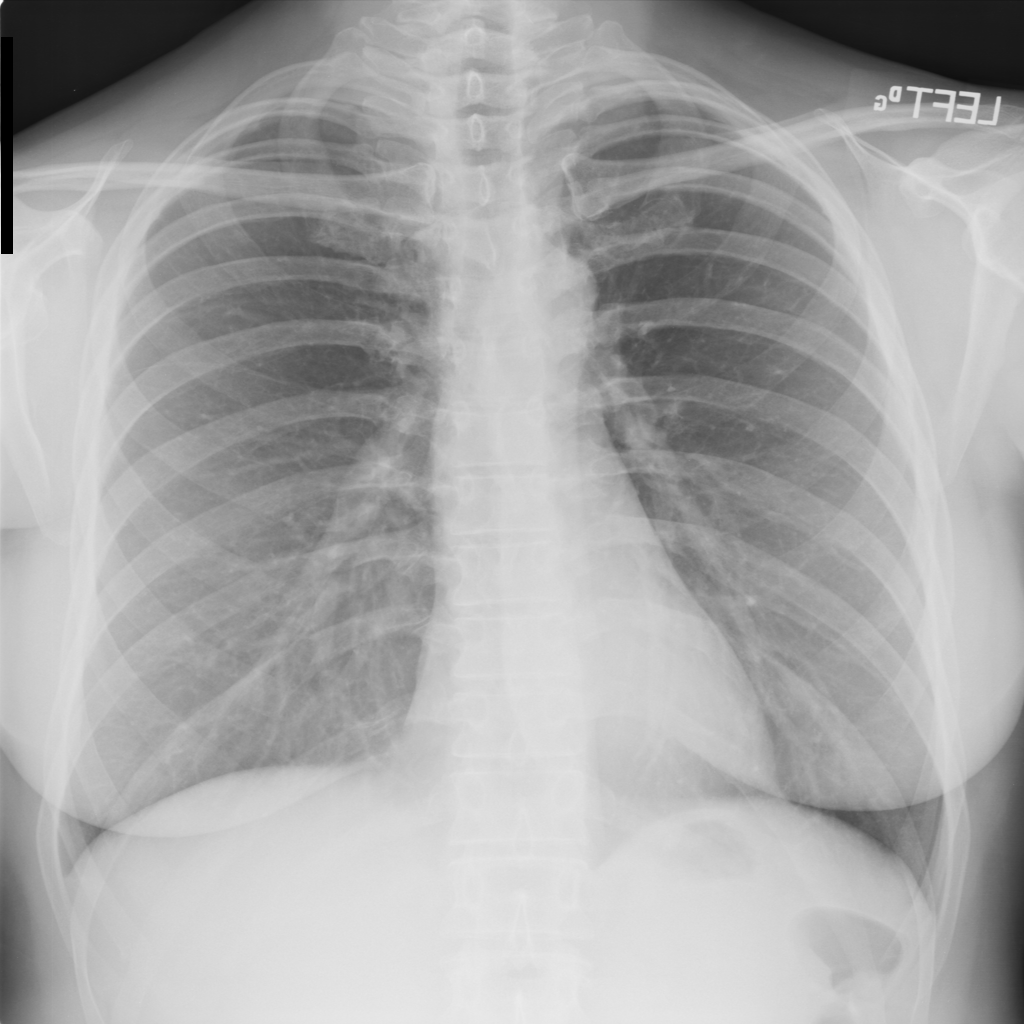

PAT-50E5 · IMG-008Mass

PAT-50E5 · IMG-008

PA